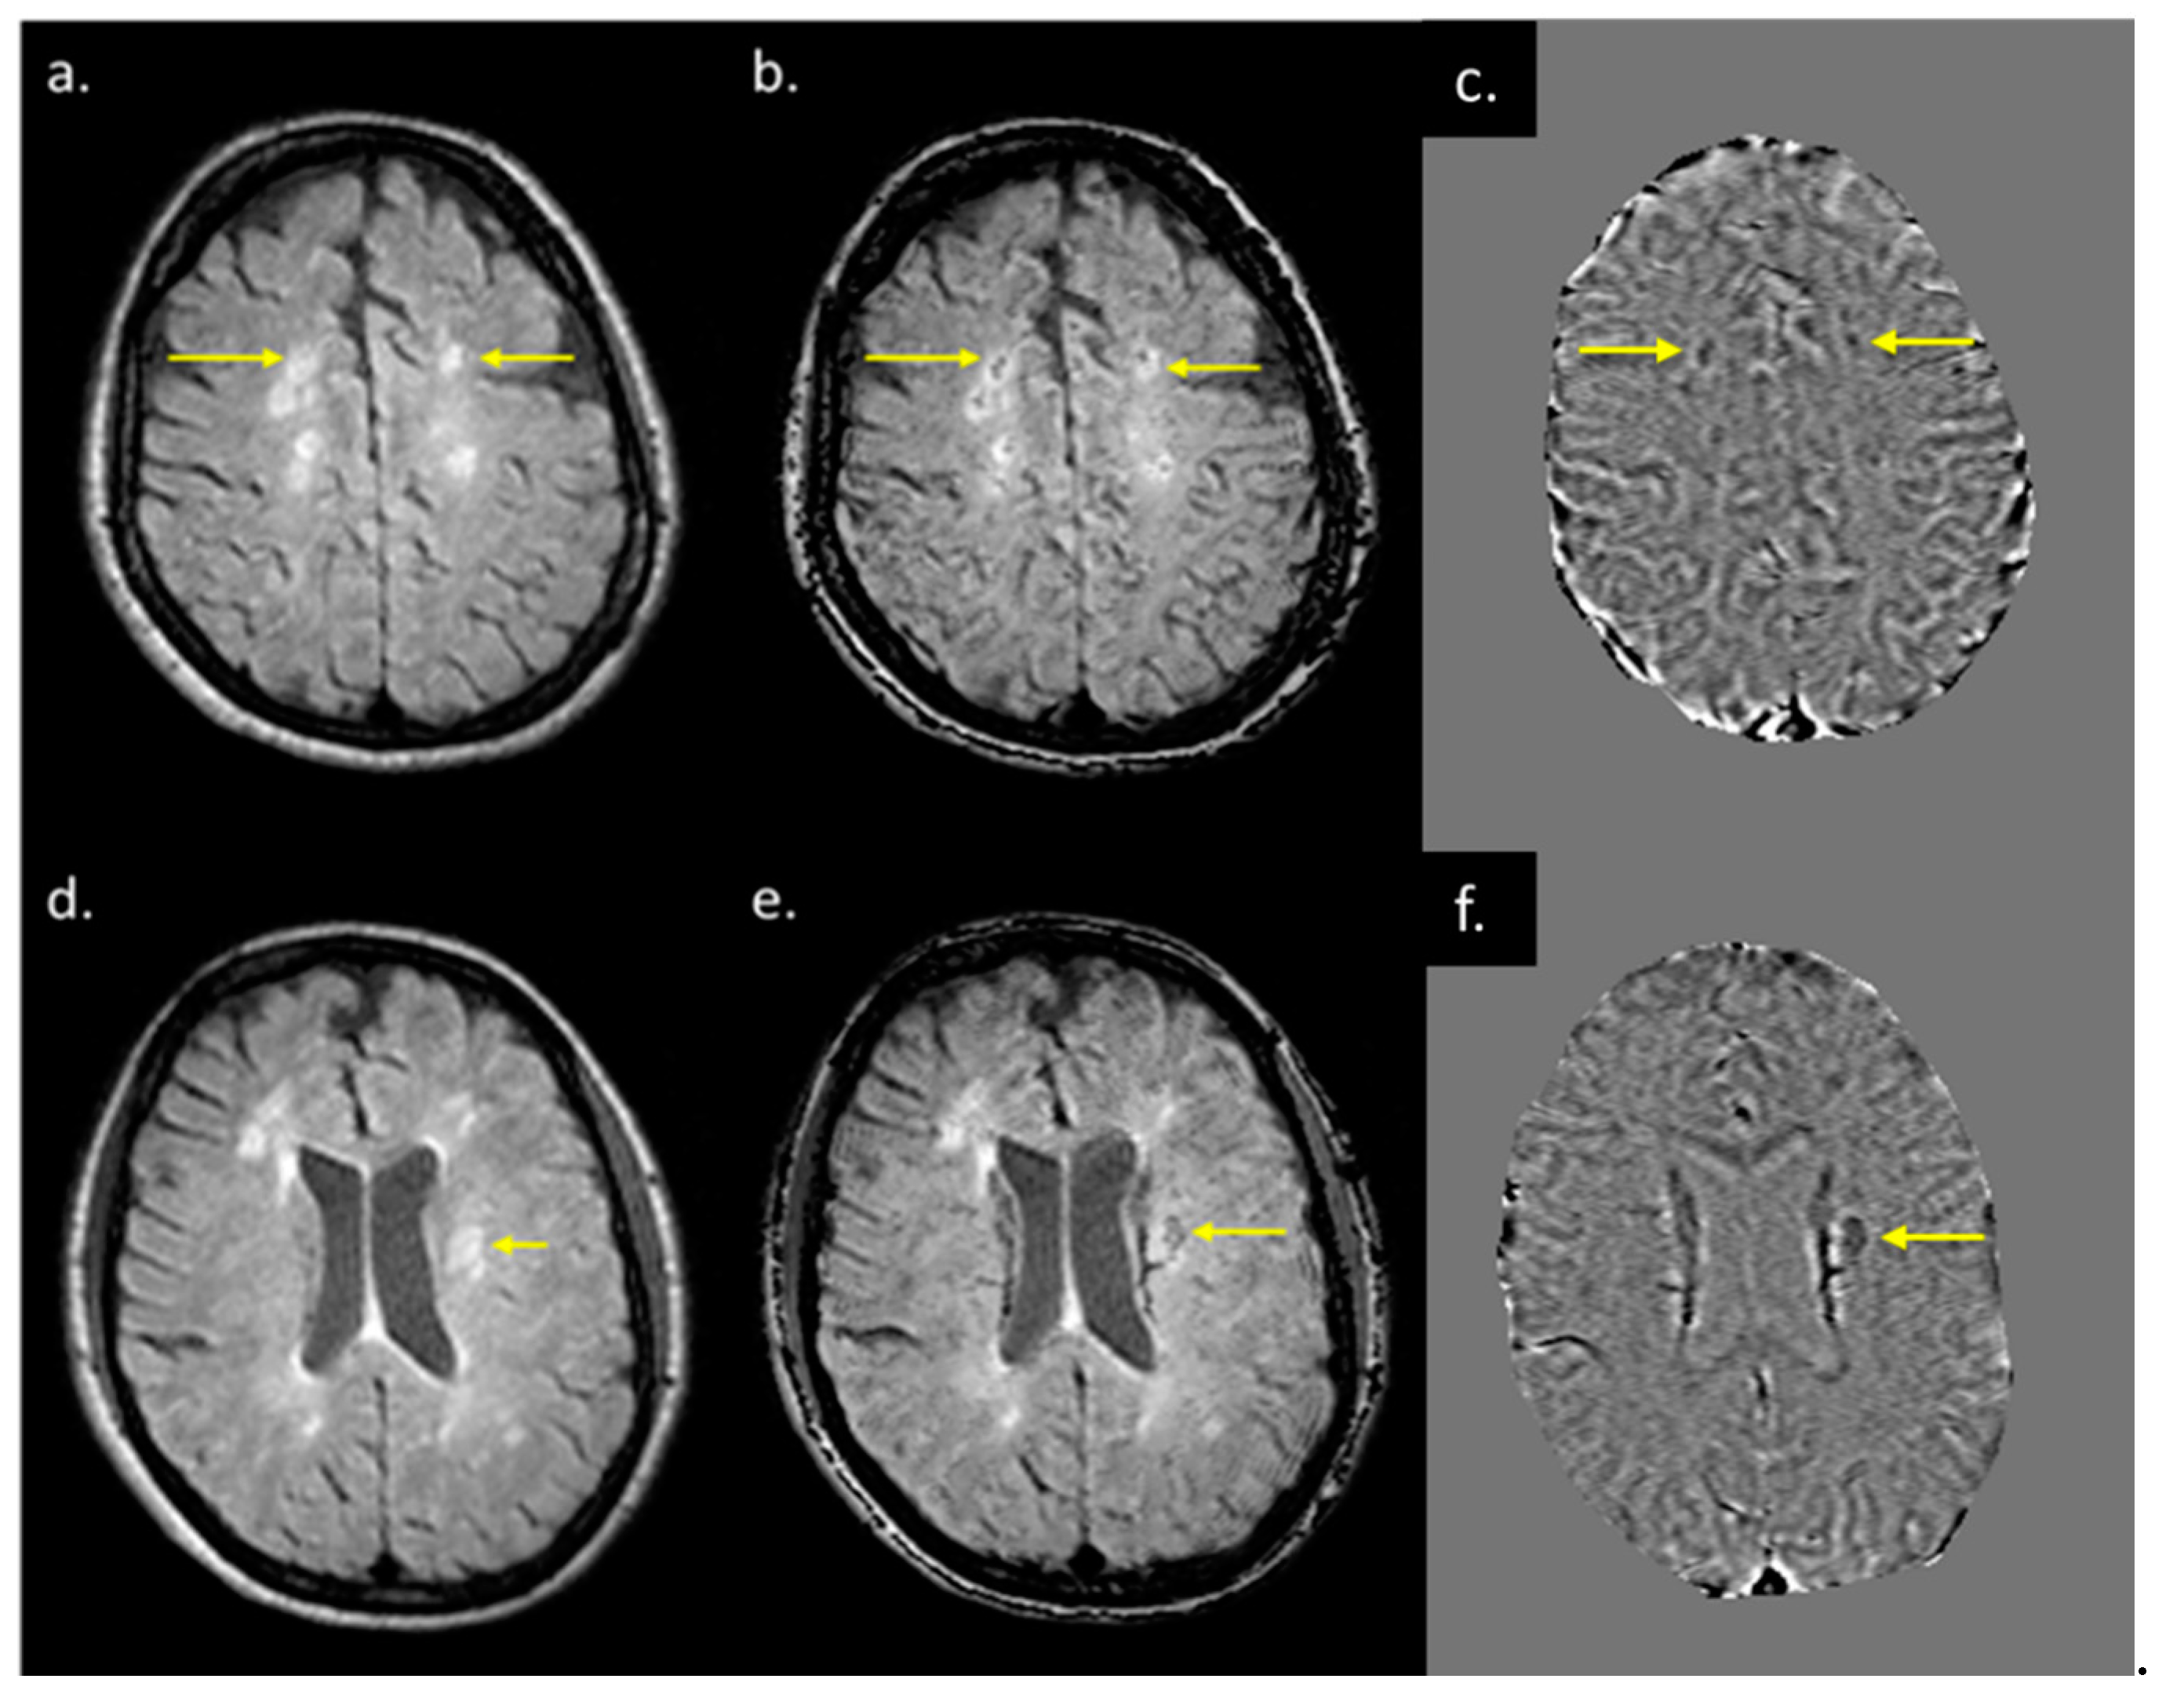

Eighteen (out of twenty) MS subjects had lesions at both time points. An example image of a typical MS lesion appearance across all modalities and their image quality is shown in Figure 2. Two of the MS subjects had no visible lesions in T2 FLAIR. The remaining eighteen MS subjects had visible deep and periventricular WMHs in T2 FLAIR. The lesion count in MS subjects varied from 2 to 84 lesions in the 18 subjects. Six subjects had lesion loads between 0.1 and 1.0 cc, eight subjects had lesion loads between 1.0 and 10 cc, and four MS subjects had diffuse WMH volume that exceeded 25 cc as measured from the T2 FLAIR data. The overall lesion burden did not change between time points in the six-month period between scans for any of the subjects.

Figure 2.

Lesion appearance in different modalities: (a) pre-contrast T1W, (b) post-contrast T1W, (c) T2WI, (d) T2 FLAIR, (e) MTR, (f) MWF, (g) QSM, (h) FA, (i) T1MAP, (j) PSDMAP, (k) T2STAR, and (l) ADC.

MWF had a thicker slice than other modalities and lower resolution, making it difficult to see smaller lesions; however, larger lesions could still be easily visualized. In total, 162 of 384 (42.2%) QSM-positive lesions and 29 of 94 (30.8%) QSM-negative lesions were visible in the MWF images. An example image showing MWF compared to other modalities is shown in Figure 7. The MWF correlated with susceptibility for QSM visible lesions, indicating that both methods were sensitive to loss of myelin fibers in white matter lesions (see Figure 8, p-value = 0.01). It can be seen from Figure 2 and Figure 7 that lesion appearance differs between modalities. FLAIR lesions are diffuse, lesions in modalities such as T1, T2WI, MTR are smaller and QSM lesions are local and have different volumes.